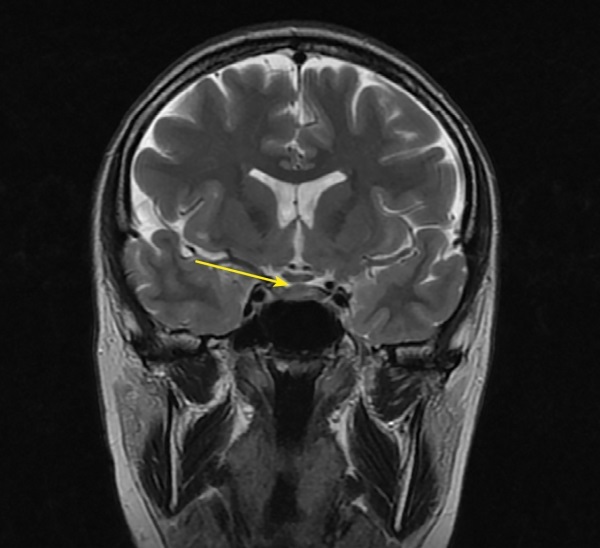

Autoimmune/lymphocytic hypophysitis is one of the rare causes of central diabetes insipidus in adults and is most common among women in the second or third trimester of pregnancy. Numerous studies have shown that lymphocytic hypophysitis is characterized by a very variable clinical signs with the development of neurological symptoms, visual disturbances and hypopituitarism with partial or complete loss of pituitary function, as well as a number of features in magnetic resonance imaging (MRI). Isolated lymphocytic indibuloneurohypophysitis occurs in fewer cases and involves the posterior lobe and stalk of the pituitary gland with a clinical presentation of diabetes insipidus. The above clinical case describes the development of hypophysitis in a pregnant woman with a predominant lesion of the posterior pituitary gland and an outcome in diabetes insipidus, which persists 6 years after pregnancy and childbirth. In the article some aspects of the differential diagnosis of diabetes insipidus in pregnant women, as well as instrumental diagnosis and treatment approaches of hypophysitis are discussed.